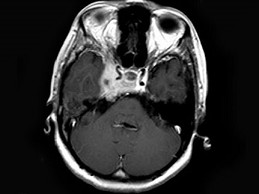

女,34岁。右侧听力下降,耳鸣2个月。MRI平扫及增强扫描如图示,最可能的诊断是 ( ) EBH-00871.jpg EBH-00872.jpg EBH-00873.jpg EBH-00874.jpg

• D.神经源性肿瘤